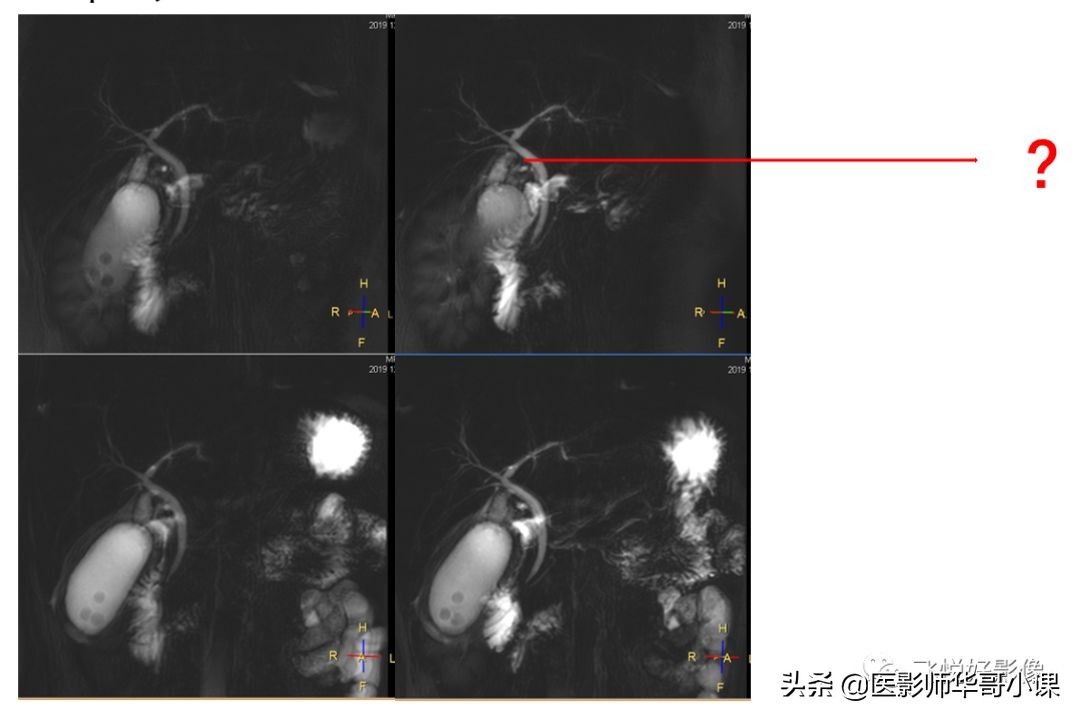

2D MRCP胆囊颈显示不清,无法重建。

3D_MRCP_BH可以进行3D重建,找到“责任病灶”。